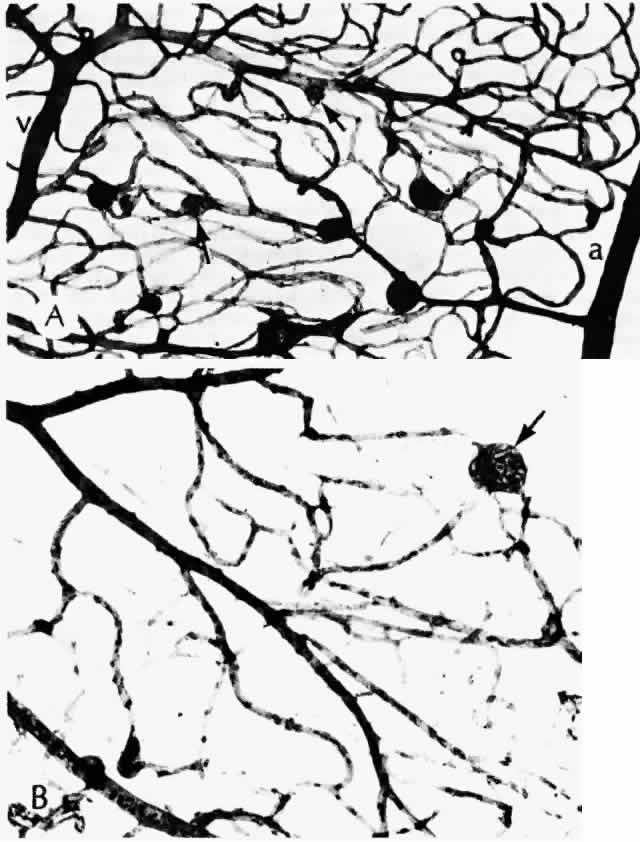

surface. In fact, it is not known what prompts the development of diabetic retinopathy, although ischemia clearly plays a role.25 Certain alterations have been observed in blood from diabetic patients, including increased rigidity and aggregation of the erythrocytes, altered platelet activity, changes in plasma proteins, and increased affinity of hemoglobin for oxygen. Both the increased aggregates of platelets and the abnormally rigid erythrocytes can occlude small blood vessels, contributing to retinal ischemia. The increased affinity of hemoglobin for oxygen means that less oxygen is released to the tissues.26 Whether tightly controlling blood sugar levels improves retinopathy or even halts its progression is controversial. In one investigation,27 dogs were made diabetic and put into three groups: good control for 5 years, poor control for 5 years, and poor control for 2½ years followed by good control for the remaining time. The third group had developed almost as many microaneurysms at 5 years as did the group under poor control for the entire time. This study indicates that tight control is maximally beneficial when undertaken early in the course of the disease. Human studies to corroborate or refute this have been understandably difficult to carry out. Transplantation of the pancreas or pancreatic islet cells is one way to normalize blood glucose by restoring endogenous insulin. In one study, eight patients who received pancreatic transplants exhibited no difference in retinopathy between the four whose transplants functioned and the four whose transplants failed.28 In another small study, the proliferative retinopathy of patients who received pancreatic transplants remained stable or worsened, despite their being euglycemic.29 Recently, results from a large prospective series, the Diabetes Control and Complications Trial, have shown that tight control, including three or more daily insulin injections or continuous infusion, based on at least four glucose determinations daily, does prevent development or progression of retinopathy to a significant degree. All patients in the primary prevention group had diabetes for 5 years or less and did not have retinopathy at the outset of the study. Thus, tight control begun early may indeed help prevent or delay the onset of retinopathy.30 As noted previously, duration of disease is a strong predictor for development of retinopathy.31,32 Prepubertal children may develop minimal retinopathy,33 but the blood-retinal barrier is altered during puberty, apparently through hormonal influence, leading to retinopathy.34 Unless the macula is edematous, nonproliferative retinopathy is asymptomatic and may be found only on routine ophthalmoscopy. In patients who develop diabetes after puberty, retinopathy may be a presenting sign of the disease. The earliest manifestation of diabetic retinopathy is the appearance of microaneurysms (Fig. 5, Color Fig. D). They appear as small red dots clinically and often are seen more readily on fluorescein angiography, where they fill and leak, with staining of the vessel wall.35 Histologically they are small “outpouchings” of the capillary vessel wall and are usually saccular but occasionally fusiform in shape. They can occur anywhere along the capillary network between the arteriole and venule.18 Some microaneurysms, however, do not fill with fluorescein and have been shown to be thin-walled capillary outpouchings filled with erythrocytes. They may represent either one stage of microaneurysm formation or a specific type of it.36 As shown by trypsin digestion, capillary pericytes are lost first,27 followed by endothelial cells (Figs. 6 and 7). Aldose reductase, one of the enzymes in the sorbitol metabolic pathway, is present in significant quantities in retinal capillary pericytes, but not in endothelial cells, and may thus be implicated in the formation of microaneurysms.37 The final result is an acellular segment of capillary that is nonperfused on fluorescein angiography.36 The normal retinal vasculature, including the capillaries, forms a barrier to the free exchange of metabolites.38 This blood-retinal barrier is damaged in diabetes, allowing leakage of larger molecules, which are clinically manifested as hard exudates and retinal edema. Ultrastructurally, the normal junctions between capillary endothelial cells are disrupted.39 Hard exudates clinically appear as shiny yellow deposits (see Fig. 5; Color Fig. D). When they surround a microaneurysm in a circular pattern, the condition is called circinate retinopathy. Histologically, the deposits accumulate at the level of the outer plexiform layer (Fig. 8, Color Fig. E) and consist of lipids, complex carbohydrates, and proteins, as demonstrated histochemically. Hard exudates are normally asymptomatic unless they involve the macula, where they cause a drop in visual acuity. If a leaking microaneurysm can be identified on fluorescein angiography, laser photocoagulation can obliterate it. Over time, the fluid is resorbed, and sometimes visual acuity can improve.40 Cystoid macular edema can be caused by many different diseases as well as diabetes. It is characterized by diffuse leakage of the capillaries in the posterior pole. In advanced cases, the cystoid spaces are ophthalmoscopically visible, resembling the petals of a flower. Cystoid edema is seen more easily on fluorescein angiography, since the spaces fill with fluorescein. Histologically, cystoid fluid is seen at the outer plexiform layer, but may also accumulate in the inner nuclear layer. The synapses of the outer plexiform layer are slanted in the fovea because the inner retinal layers are pushed away from the foveal pit. Because of these slanted connections, this area can be distended by fluid more readily. Ultrastructurally, the fluid appears to be located within Müller cells, and there is evidence of capillary endothelial damage.41 In some patients, the cystoid spaces can coalesce, forming lamellar or full-thickness macular holes.42 Other nonproliferative changes include intraretinal hemorrhages. Flame-shaped hemorrhages occur in the nerve fiber layer, and dot-blot hemorrhages occur in deeper retina, in the outer plexiform and inner nuclear layers (Fig. 9). Nonproliferative retinal changes that have been associated statistically with an increased likelihood of development of proliferative retinopathy have sometimes been termed proproliferative retinopathy. These changes indicate an increased level of retinal ischemia. Cotton-wool spots are areas of capillary closure. The ischemic axons swell, with resultant loss of retinal transparency. They occur frequently in diabetics with and without hypertension.43 Clinically, they appear as white, feathery spots, commonly at the bifurcation of retinal vessels. On fluorescein angiography, these areas appear dark, both because of focal capillary closure and nonperfusion, and because the focal retinal swelling obscures the subjacent choroidal fluorescence. Histologically, the axons of the nerve fiber layer are focally swollen in a fusiform configuration and have been called cytoid bodies because the central density superficially resembles a cell with its nucleus.44 Depending on the severity of the ischemia, individual ganglion cells may recover or be lost.20 Capillary dropout in the fovea is an important cause of untreatable visual loss, even if there is no macular edema.43 The foveal avascular zone is significantly larger and more irregular in contour in patients with diabetic retinopathy than in control patients,45 even when the patients have no clinical visual loss.43 The retinal arterioles may become narrowed and irregular. Patients with diabetes are likely to have arteriosclerotic changes in the retina as well as systemically. The arterial wall is thickened, with resultant narrowing of the blood column. Clinically, this narrowing is manifest as a “copper-wire” change and with greater severity, as a “silver-wire” change. These descriptions reflect the narrowed and relatively less visible column of erythrocytes. Even severely narrowed, silver-wire arterioles, however, may still allow some passage of fluorescein. The arterioles may ultimately become occluded,20 and this phenomenon can proceed rapidly, with accompanying capillary dropout.43 Extensive capillary and arteriolar nonperfusion can be even more prominent in the midperipheral retina than posteriorly.46 The retinal veins can also become irregular and tortuous with sausage-shaped dilatations. The vascular walls become diffusely permeable so that they both leak and stain with fluorescein. These changes also seem to be associated with ischemia. As shown by trypsin digestion, the beaded areas are hypercellular (Fig. 10).43 Diabetes is also a risk factor for branch retinal vein occlusion47 and central vein occlusion.43 Other capillary changes, more severe and extensive than microaneurysms, are collectively termed intraretinal microvascular abnormalities (IRMAs). Clinically, these manifest as dilated channels that leak fluorescein and show vascular wall staining (Fig. 11). De Venecia and co-workers36 were able to distinguish between IRMAs arising from arteriolar capillaries and IRMAs arising from venular capillaries. The IRMAs associated with arterioles exhibited early filling and late leakage on angiography. Histologically, they appeared as solid proliferations of endothelial cells, adjacent to acellular capillaries. In some instances, they may represent true intraretinal neovascularization. The IRMAs adjacent to venules filled in the early venous phase and leaked late. Histologically, they were irregularly dilated, had thin walls, and may have represented shunts.

All of these changes are forerunners of proliferative retinopathy. Patients are unlikely to develop proliferative retinopathy before 10 years' duration of diabetes, but thereafter the incidence rises steadily.31,32 Rarely, proliferative retinopathy with vitreal hemorrhage can be the presenting sign in younger patients.48 As in other diseases associated with retinal neovascularization, the stimulus for new vessel formation in diabetes appears to be ischemia. The retina is uniquely dependent on oxygen: its demand on a unit-to-weight basis exceeds that of all other tissues, including the brain.7 A number of growth factors may act on the retina, including somatomedin C (insulin-like growth factor I), platelet-derived endothelial growth factor, fibroblast growth factors, angiogenin, and others.49 According to one recent study of samples of neovascular membranes obtained at vitrectomy from diabetic patients, only vascular endothelial growth factor was present in all specimens.50 This same factor is also present at significantly higher levels in the vitreous in eyes with proliferative retinopathy than in those without the disease.51 The precise role of the different factors in the promotion of neovascularization remains to be elucidated. New vessels that develop on or within a disc diameter of the optic nerve head are termed new vessels at the disc (NVD) (Color Fig. F). Those that develop anywhere else on the retina are called new vessels elsewhere (NVE). NVD indicate a diffuse retinal ischemia, whereas with NVE, the ischemia may be more localized, occurring at a site of previous arteriolar closure or capillary dropout. NVE can occur peripherally as well as in the posterior pole.52 Histologically, new vessels develop between the retinal surface and the posterior surface of the formed vitreous (Fig. 12). With NVE, there is a demonstrable break through the internal limiting membrane (Fig. 13).20 Early-developing new vessels have lumina even at the proliferating tips.53 Active new vessels have endothelial cells and pericytes, with fenestrations. Morphologically, fenestrations are areas ranging from 40 to 80 nm in diameter where the cell membranes are focally fused, and are normal findings in capillaries outside of the retina and brain. They allow increased permeability and are responsible for the diffuse leakage of fluorescein seen from new vessels on angiography. Inactive or “ghost” new vessels are acellular, having lost both endothelium and pericytes.39 With time, fibrous tissue develops and accompanies the new vessels. The vessels themselves may leak and bleed into the vitreous, leading to visual loss. The fibrous tissue is contractile, and has been shown to contain actin filaments.54 Clinically, fibrous proliferation appears as whitish bands on the retinal surface, sometimes obscuring the neovascularization. With retinal elevation, retroretinal membranes also can form. Traction can cause cystoid changes in the retina20 and venous loops,55 as well as retinal detachment (Color Fig. G). Extensive traction can cause macular heterotopia reminiscent of retinopathy of prematurity.56 Histologically, the cells in the membranes appear to be fibrous astrocytes. At least in some cases, however, there is immunohistochemical evidence that cells of Müller can also migrate and form membranes. Intraretinal migration and replacement of outer retinal layers by cells of Müller can appear clinically as retroretinal proliferation.57 Other cells found in preretinal membranes include inflammatory cells (i.e., lymphocytes, plasma cells, and macrophages) and retinal pigment epithelial cells.58 Panretinal photocoagulation, usually accomplished with an argon laser, is used to treat neovascularization of the retina and iris. The Diabetic Retinopathy Study Research Group59 has established the efficacy of this procedure in preventing severe visual loss, a measure that appears to last for at least 15 years.60 Radiant energy in the visible spectrum passes through the transparent retina and is absorbed by melanin pigment, hemoglobin, or both, depending on the wavelength chosen. The result is a focal scar of the outer retina, or if intense enough, full-thickness retina (Fig. 14).61 Full-thickness scars can cause extensive visual field loss because of obliteration of the nerve fiber layer.20 The choriocapillaris is effectively closed by photocoagulation, as demonstrated by studies of vascular casts.62 After panretinal photocoagulation, the oxygen tension on the inner retinal surface is greater over areas of scarring compared with adjacent areas of intact retina, presumably due in part to greater oxygen diffusion from the larger vessels of the choroid. The increased oxygen levels appear to alleviate retinal ischemia and help explain how photocoagulation causes retinal neovascular regression.63 This finding has been substantiated by direct measurements of oxygen tension in human patients undergoing vitrectomy.64 In the juxtafoveal area, krypton red was associated with less inner retinal damage than argon green.65,66 This is of clinical importance in the treatment of macular edema. The wavelength used, however, appears to be unimportant in extrafoveal areas of the retina.66 Macular grid photocoagulation has been proposed as an effective way to treat macular edema when specific leaking points cannot be identified. In animal studies, this technique appeared to work by occluding some capillaries and reducing the lumen in others, thereby decreasing the ratio of the retinal capillary area to the retinal area. The photoreceptors and retinal pigment epithelium were initially damaged but later recovered.67 |